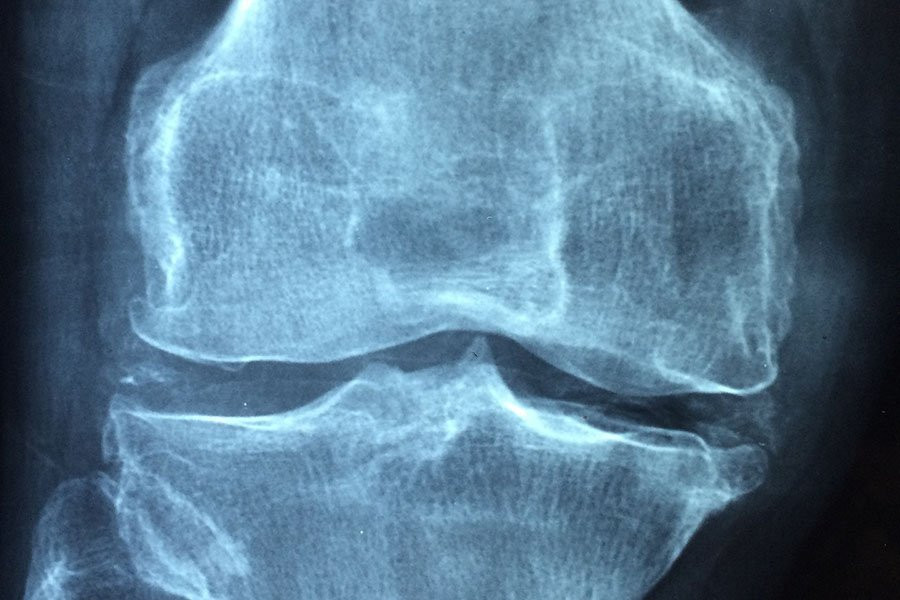

Фото из открытых источников